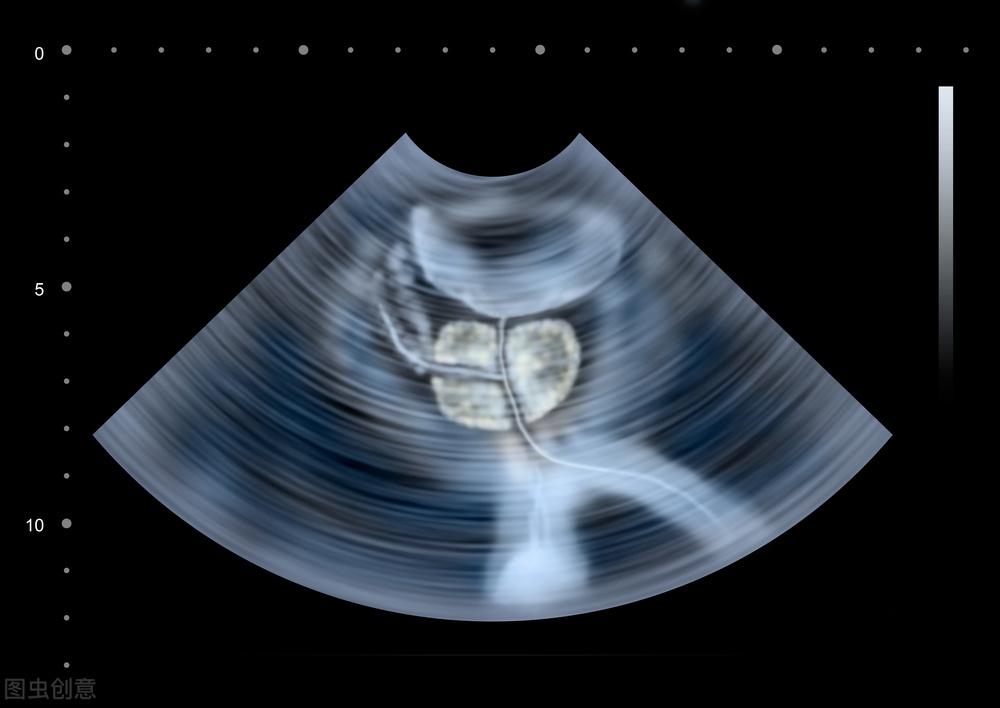

在就医时,医生通常会进行直肠指诊、尿常规检查、前列腺特异性抗原(PSA)检测、B超检查等,必要时还会进行尿流率测定和尿动力学检查。这些检查可以帮助医生全面了解病情,制定合适的治疗方案。